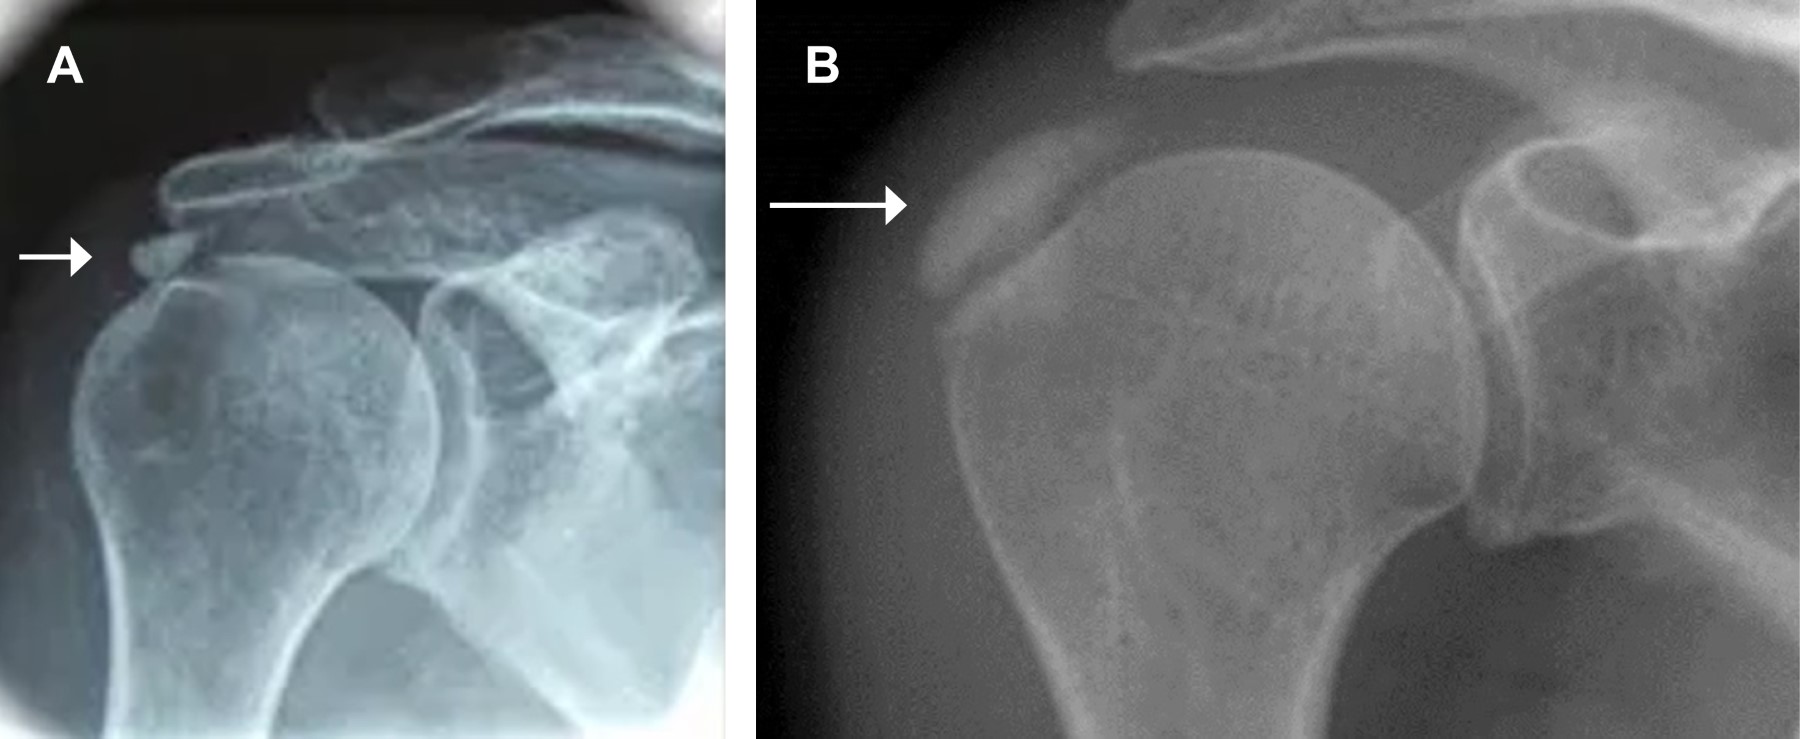

Para clasificar a la TC se han propuestos diferentes métodos, en cuanto a la severidad de los síntomas en: aguda, sub aguda y crónica propuesta por Depalma13 en 1961; en 1988, Patte y Goutallier14 describieron una clasificación según la evolución en dos grupos: el tipo I con apariencia homogénea y resolución espontánea, y el tipo II con apariencia heterogénea caracterizado por cronicidad; desde el punto de vista de la acumulación de calcio, se mencionan 4 tipos: el tipo A con calcificación de bordes bien definidos y apariencia homogénea (Figura 1A); el tipo B de bordes difusos y apariencia homogénea (Figura 1B); el tipo C de bordes bien definidos y apariencia heterogénea y; el tipo D de bordes difusos y apariencia heterogénea.

Los estudios por imágenes confirman el diagnóstico, incluso en casos asintomáticos, y se usan también para realizar el seguimiento. Las radiografías AP verdadera de hombro, lateral de escápula y outlet de hombro, son las utilizadas para determinar la extensión, localización y diseminación de la lesión del supraespinoso. Las radiografías AP en rotación externa permiten valorar al subescapular, mientras que la imagen AP en rotación interna detecta acumulación de calcio en el redondo menor e infraespinoso.16 El ultrasonido diagnóstico muestra mayor sensibilidad en detectar calcificaciones en el manguito, con la desventaja de ser dependiente del operador.17 La tomografía computarizada permite la localización más específica de los depósitos calcáreos, por otra parte el uso de la resonancia magnética es superior para determinar la existencia de otras lesiones y del estado del tendón18 (Figura 2).

Figura 1